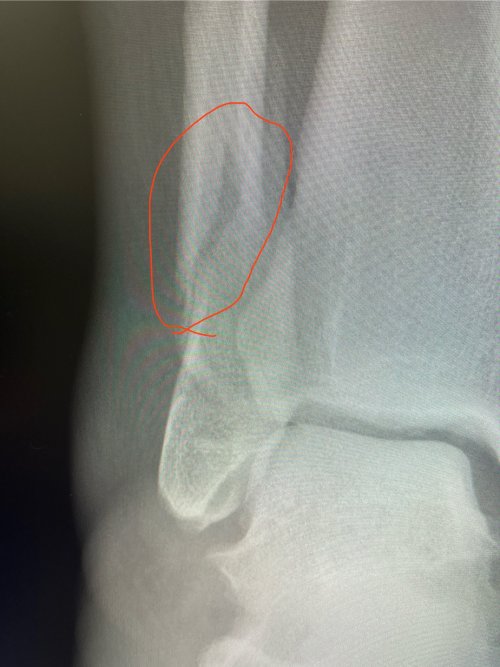

Well after a quick exam and in house X-rays they showed me a spiral fracture just above the distal end of the fibula.